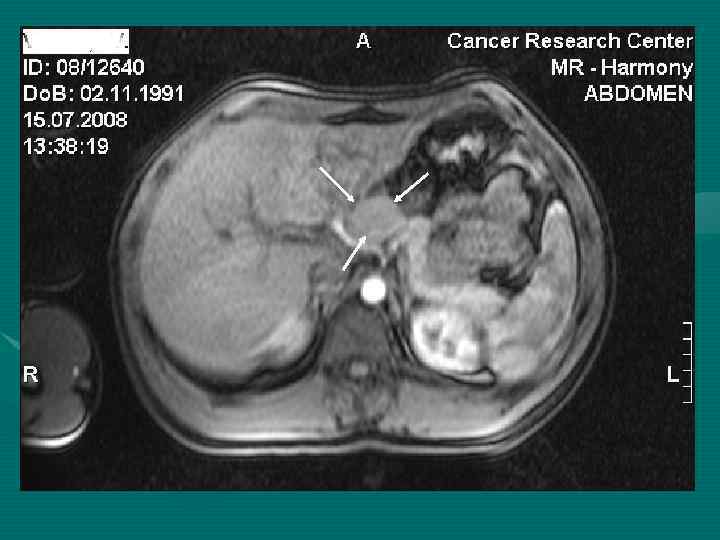

МРТ диагностика с ПРИМОВИСТОМ

КТ больного А. М. Г. до химиотерапии и через 3 месяца До начала химиотерапии – март 2008 г. После 4 курсов химиотерапии - июнь 2008 г.